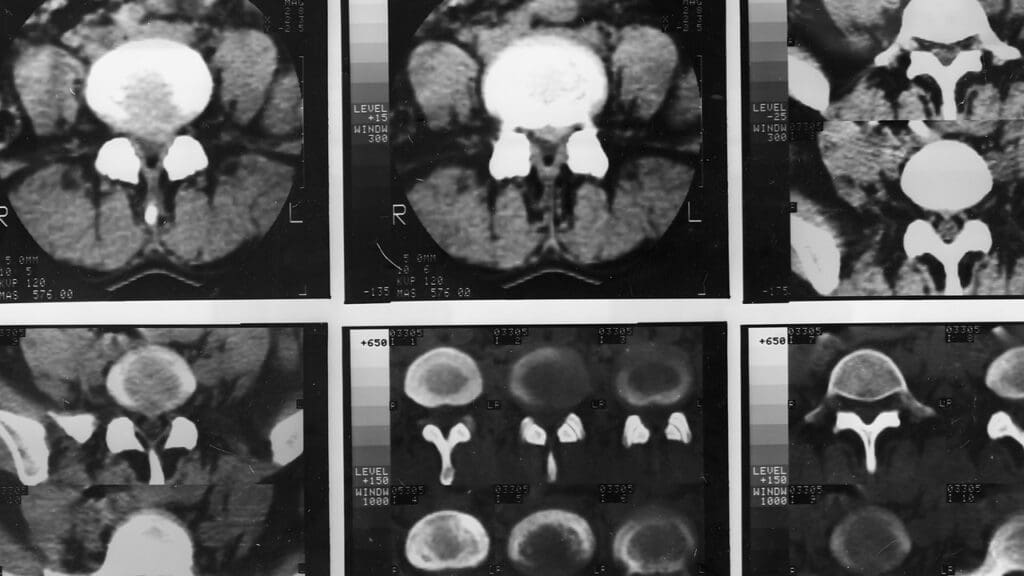

What does a brain tumor look like?

Brain tumors look different based on their type and where they are. Tests like MRI or CT scans help doctors see and diagnose them.